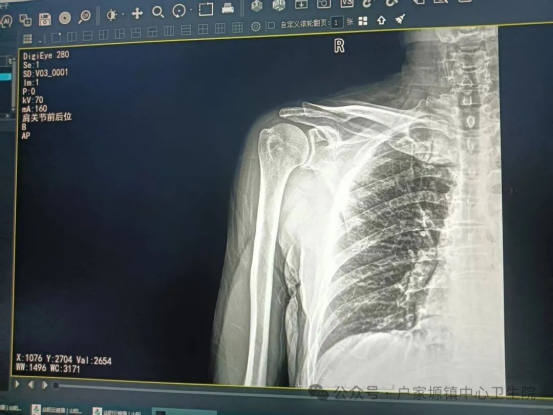

患者就诊时,肩关节明显畸形、疼痛剧烈,活动完全受限,情绪十分焦虑。接诊医生立即对患者进行详细查体及影像学检查,明确诊断为新鲜肩关节脱位,排除骨折、神经血管损伤等禁忌证后,迅速通知我院外科团队,制定了安全高效的手法复位方案。